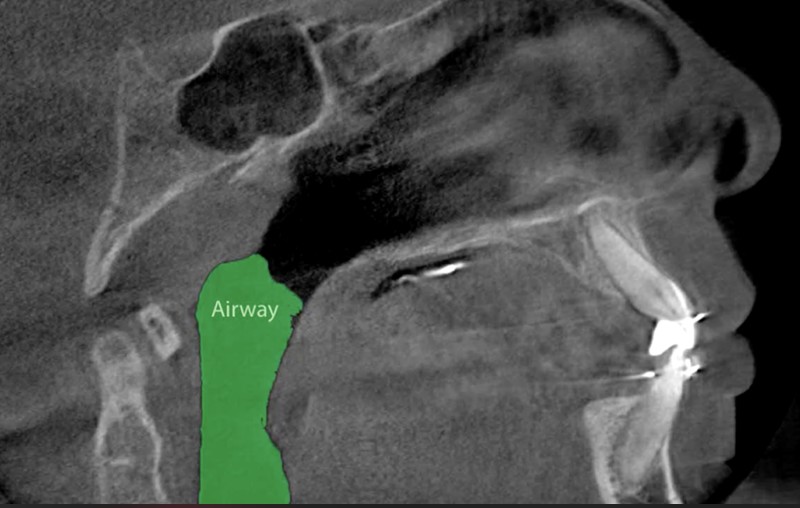

We’re excited to share a testimonial from one of our dedicated patients’ moms! In this video, she shares the amazing transformation her son has experienced after completing orofacial myofunctional therapy with Courtney and phase 1 functional orthodontics with Dr. Jake.

✨ Key Improvements:

- Increased airway volume 🌬️